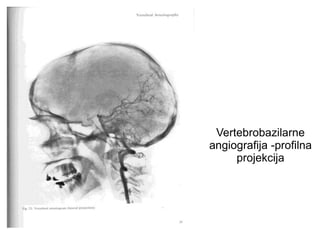

Vertebrobazilarne

angiografija -profilna

projekcija